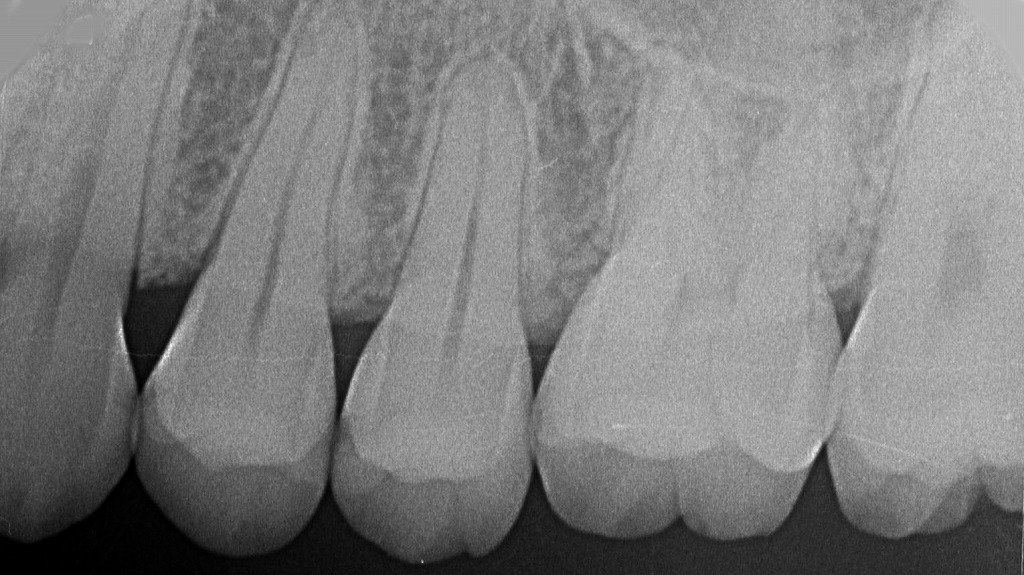

歯科レントゲンは特に安心できる理由🦷

歯科のレントゲン撮影は、医科のCTや大きなレントゲンに比べて被ばく量がとても少ないのが特徴です。

- 放射線量がきわめて少ない → 数日間の日常生活で浴びる自然放射線よりも低いこともあります。

- 防護エプロンを使用 → 鉛入りのエプロンでお腹を覆い、胎児を守ります。

- 照射部位が頭部中心 → 胎児には直接当たりません。

このため、妊婦さんでも安全に受けられるケースがほとんどです😊。